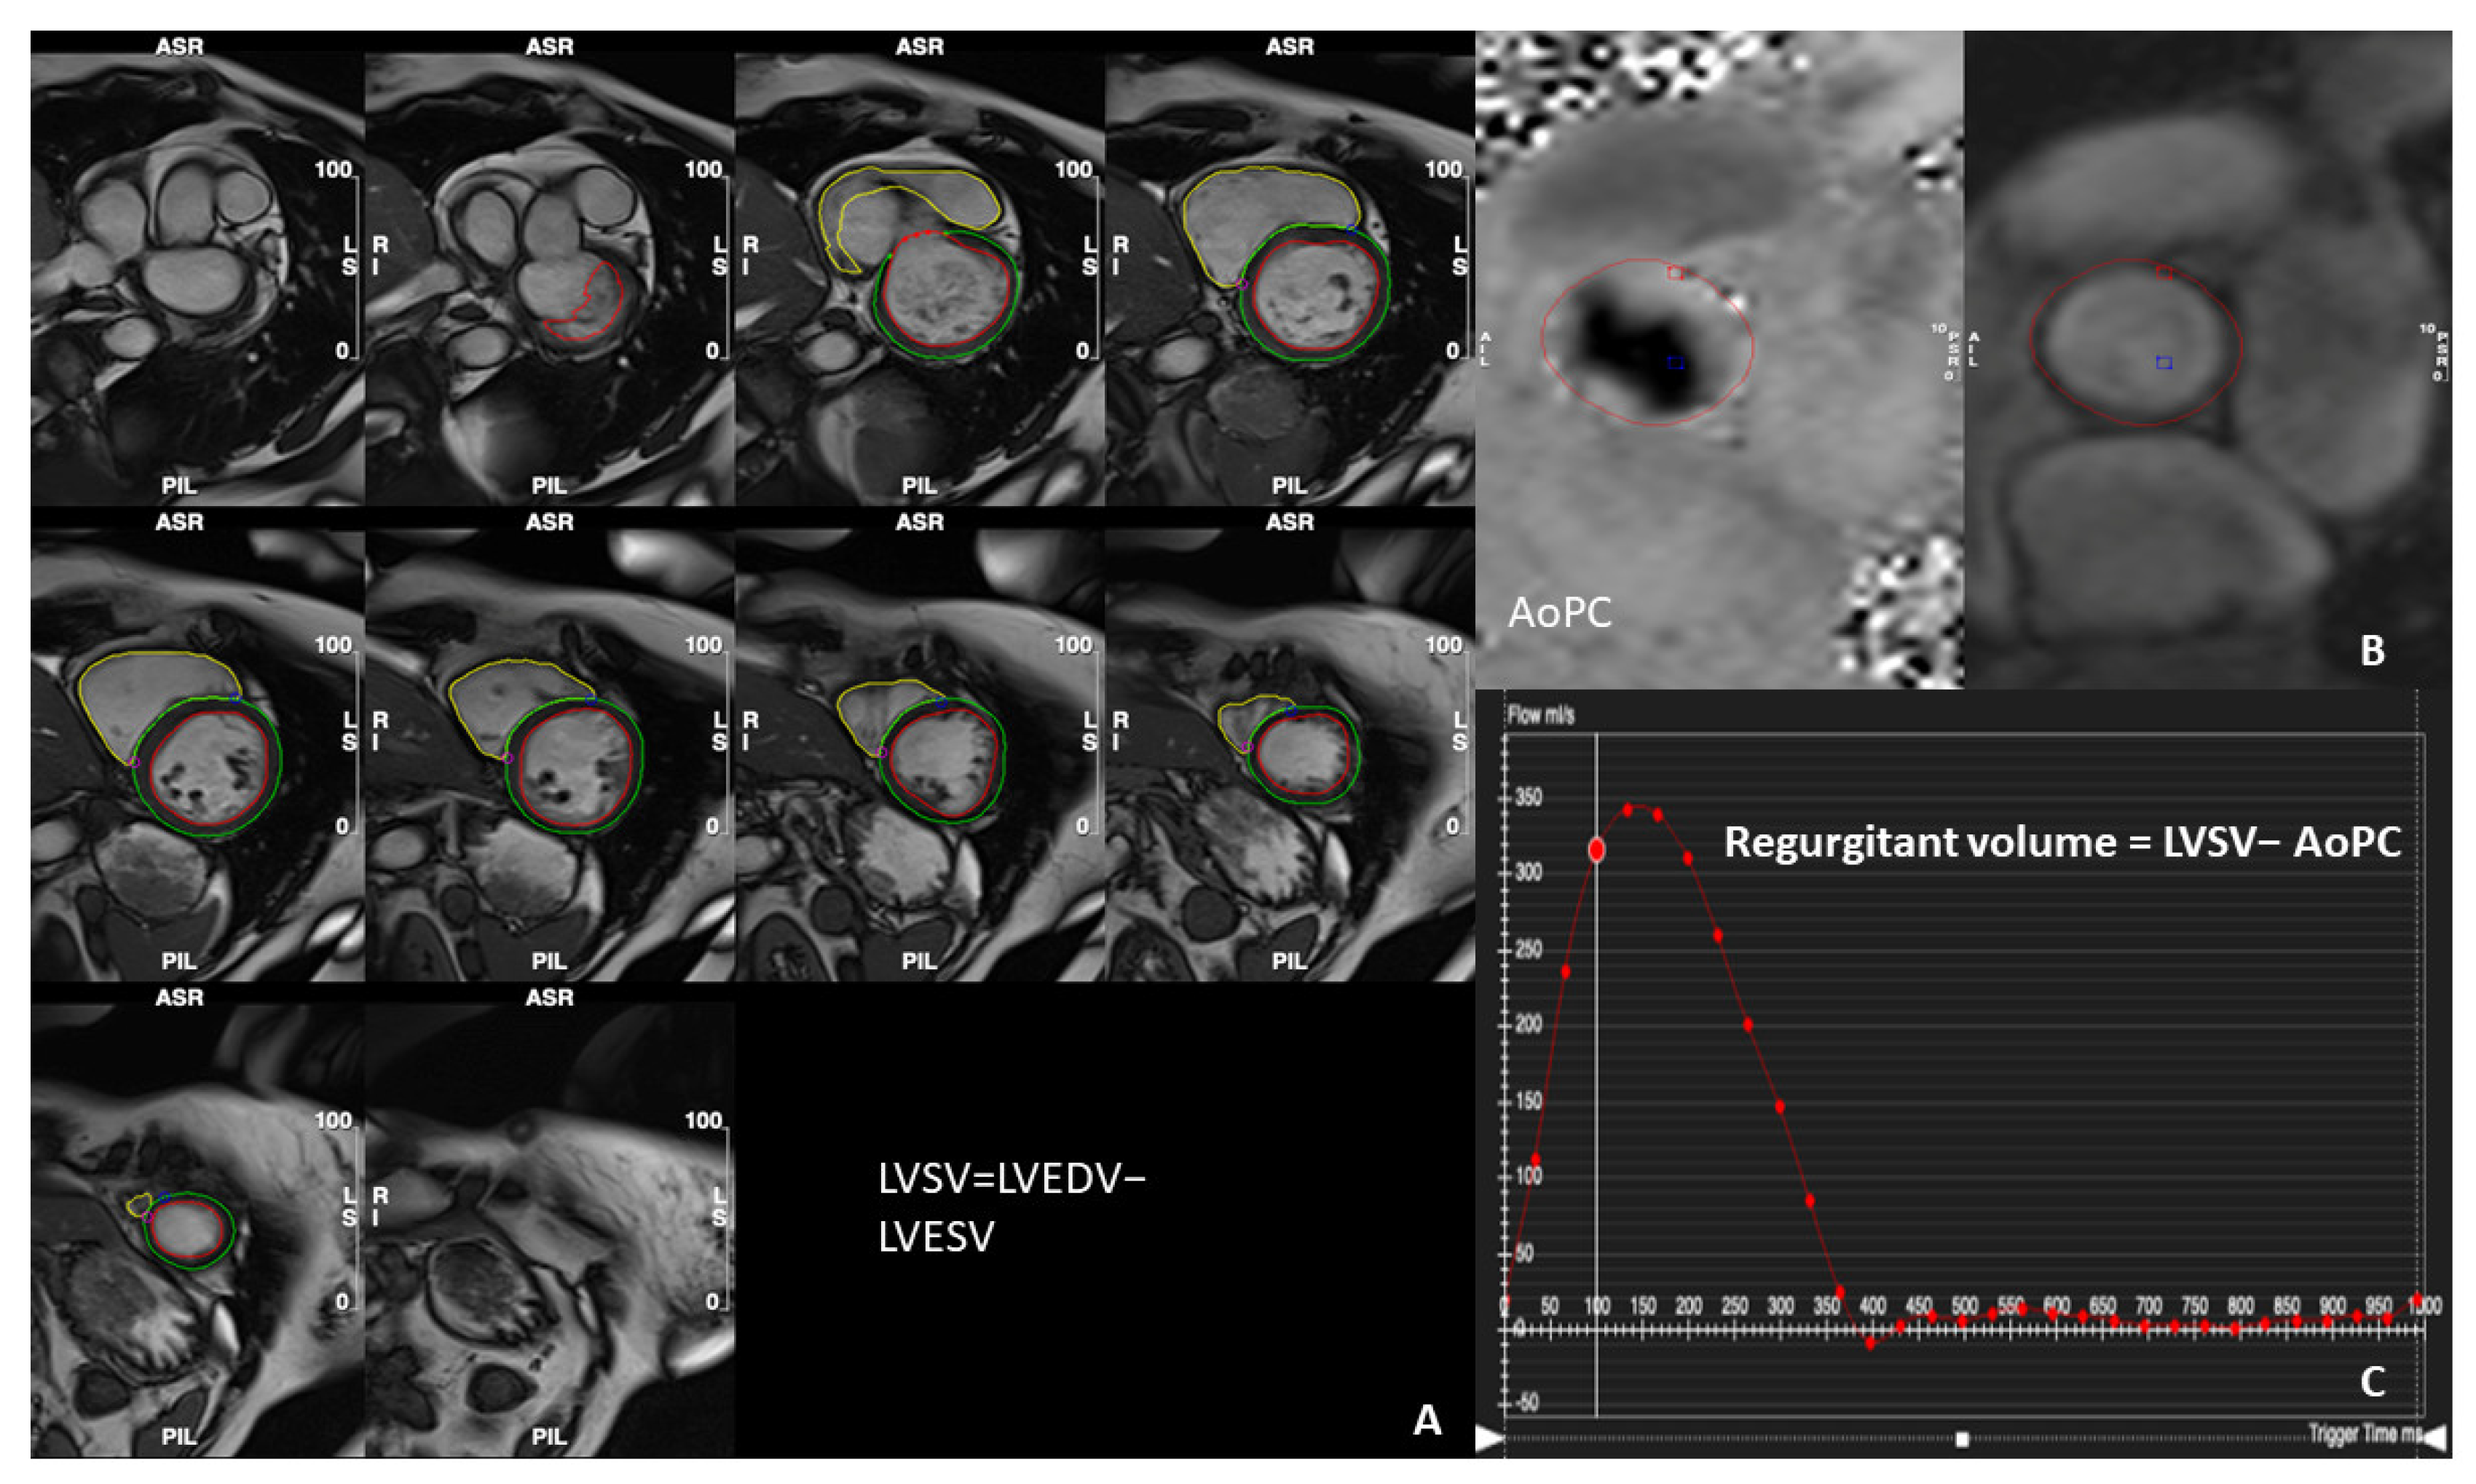

2. How to Assess Mitral Regurgitation with CMR

3. Determination of the Severity of MR Using CMR Parameters